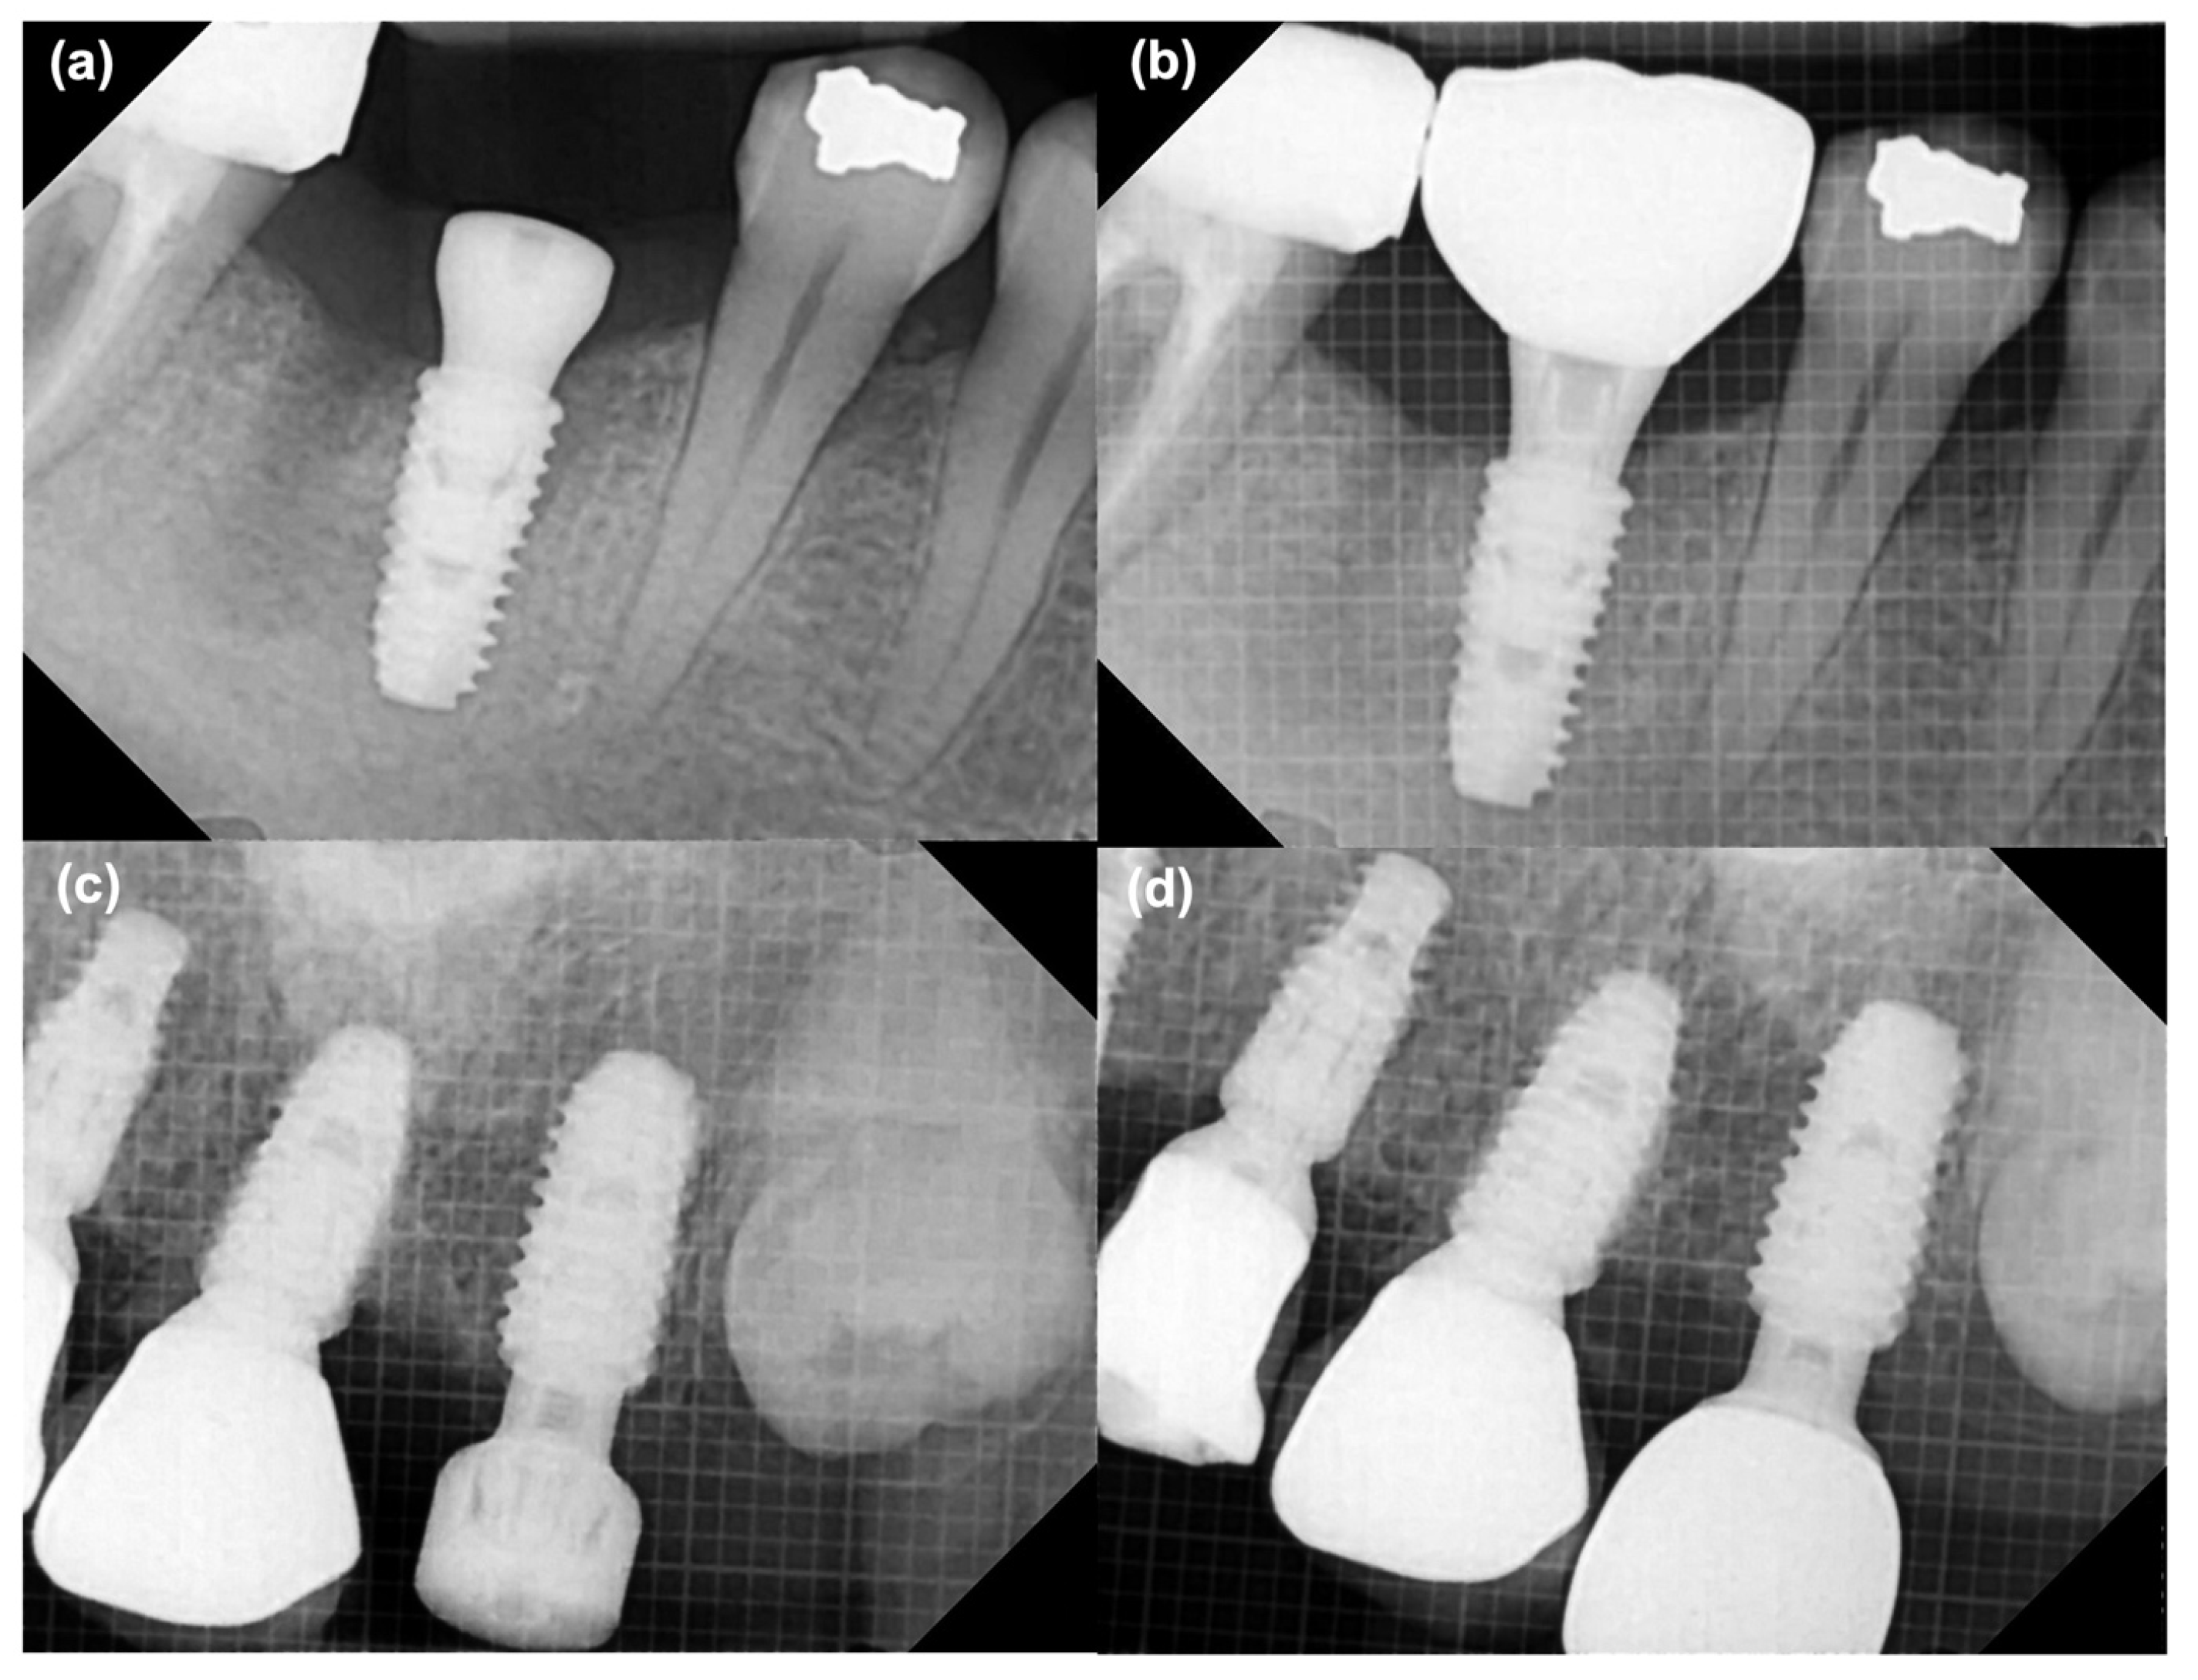

2.4.4. Marginal Bone Loss (MBL) Changes

MBL around the implants was assessed using standardized periapical radiographs. Baseline bone levels were recorded immediately after implant surgery and reassessed at the time of definitive prosthesis placement. Radiographic evaluation was performed as the vertical distance from the implant shoulder to the crestal bone level on both the mesial and distal aspects of each implant. Changes in bone height between the impression stage and prosthesis delivery were calculated to quantify marginal bone remodeling. Representative examples of the measurement process are shown in Figure 6.

3.4. MBL

Marginal bone loss averaged 0.71 ± 0.33 mm in the control group and 0.47 ± 0.28 mm in the test group, with a significant difference favoring the digital workflow (p < 0.05) (Figure 10). Intra-examiner reliability for MBL measurements demonstrated an ICC of 0.88.

Figure 6. Periapical radiographs showing measurement of marginal bone levels at the time of implant impression and at the time of prosthetic placement. (a) Control group at baseline, (b) Control group at prosthesis placement time, (c) Test group at baseline, (d) Test group at prosthesis placement.